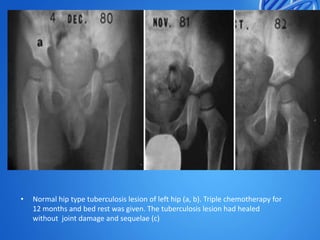

Normal hip type tuberculosis lesion of left hip (a, b). Triple chemotherapy for

12 months and bed rest was given. The tuberculosis lesion had healed

without joint damage and sequelae (c)

• Normal hip typetuberculosis lesion of left hip (a, b). Triple chemotherapy for 12 months and bed rest was given. The tuberculosis lesion had healed without joint damage and sequelae (c)